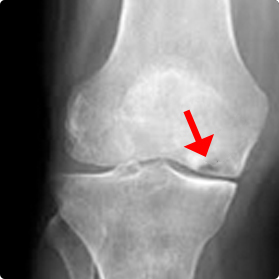

Avascular necrosis or Osteonecrosis is the death of bone tissue due to a lack of blood supply. It leads to tiny breaks in the bone and the bone's total collapse.